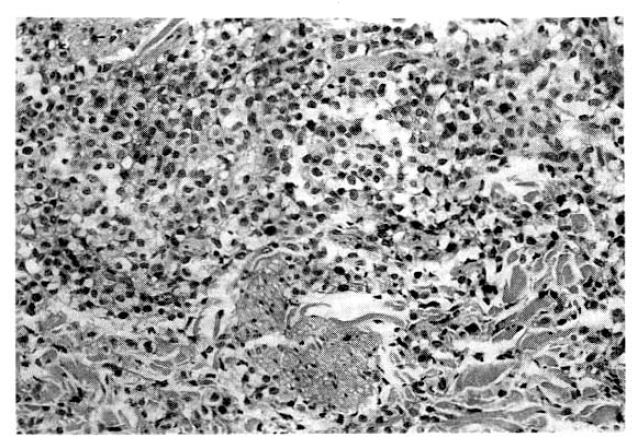

Fig. 1.

Histologic findings of lymph node show large pleomorphic tumor cells with irregular nuclear profiles and abundant dense cytoplasm (H & E stain, ×400).

Laboratory evaluation revealed hemoglobin of 7.4g/dl, hematocrit of 22.4 percent, leukocyte of 14,600/mm3 with 66 percent neutrophils and 8 percent lymphocytes and platelet 300,000/mm3. The erythrocyte sedimentation rate was 71 mm/hour. Results of serum chemistry test were normal with exception of LDH 1003.3IU/I, BUN 29.9mg/dl, creatinine 1.9mg/dl. The electrocardiography was normal. Radiologic examination of chest revealed fibrostreaky densities in right upper lobe and CT scan of abdomen showed no intra-abdominal lymphadenopathy. Biopsy of cutaneous lesions on anterior chest wall and bone marrow aspiration and biopsy were performed. Light microscopic examination of skin specimen showed that the dermis was diffusely infiltrated with large pleomorphic tumor cells, which were strongly positive for Ki-1 immunohistochemical stain (Fig. 3, 4). Electromicroscopic examination revealed convoluted nuclei with prominent nuclei and sparse intracytoplasmic organelles (Fig. 5). Bone marrow aspiration and biopsy showed a focus of collection of atypical cells with complete necrosis, suspicious for involvement of malignant lymphoma. On diagnosis of relapsed Ki-1-positive anaplastic lymphoma stage IV, we performed salvage chemotherapy with cisplatin, dexamethasone, mitoxantrone and etoposide but, unfortunately, he died of persistent pancytopenia, followed by sepsis.